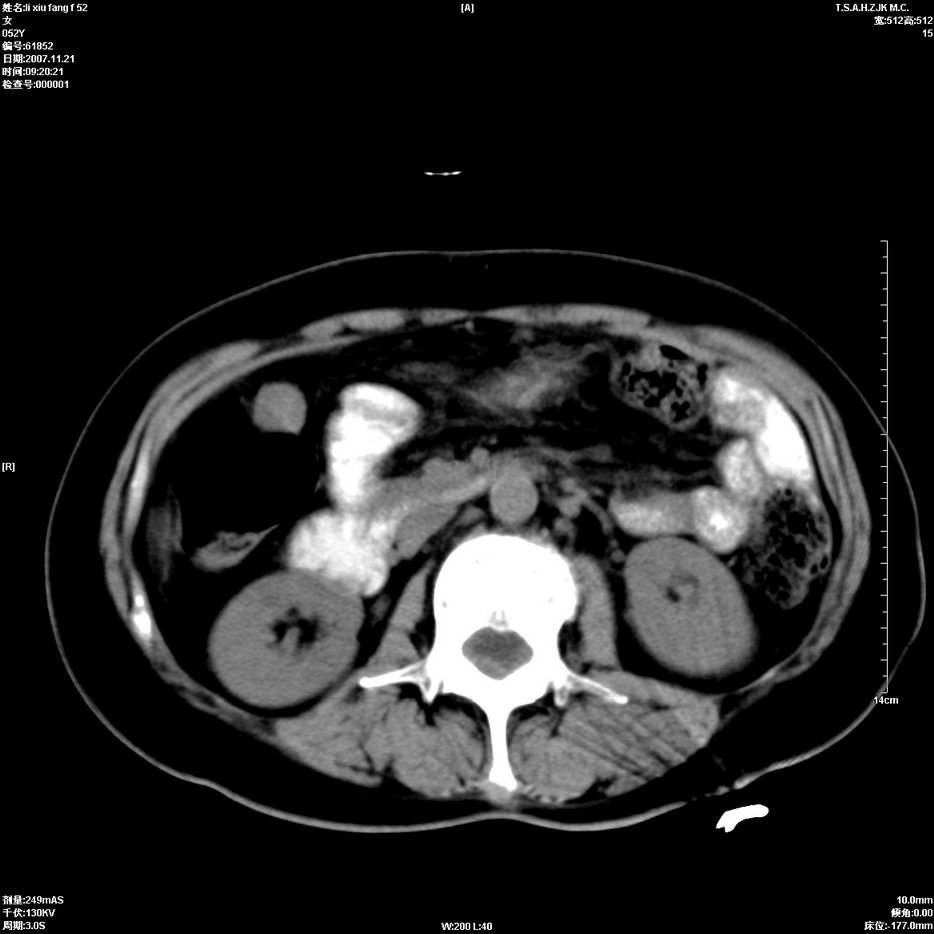

标题: CT12858:女,52岁,胎甲球蛋白861肝左叶占位,肝癌。下腔静 [打印本页]

标题: CT12858:女,52岁,胎甲球蛋白861肝左叶占位,肝癌。下腔静

肝左叶巨大低密度灶肿块,增强符合快进快出表现,有动静脉交通支;静脉期,下腔静脉内有充盈缺损,afp明显升高,支持肝癌并下腔静脉癌栓形成。

支持楼主   门静脉主干及左支癌栓形成

以下是引用拾荒者在2008-4-15 22:57:00的发言:[br]肝左叶巨大低密度灶肿块,增强符合快进快出表现,有动静脉交通支;静脉期,下腔静脉内有充盈缺损,afp明显升高,支持肝癌并下腔静脉癌栓形成。